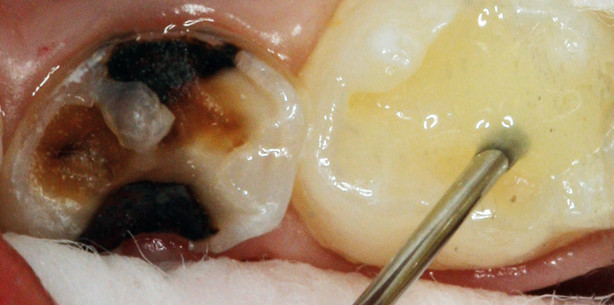

Der folgende Fall zeigt die klinische Anwendung von Venus Bulk Fill in Kombination mit dem selbstätzenden Adhäsiv iBOND® Self Etch. Ein dreijähriges Mädchen wies im Seitenzahnbereich sowohl am Milchzahn 75 als auch an 74 kariöse Läsionen auf (Abb. 1). Aufgrund der mangelnden Compliance und des umfangreichen Sanierungsbedarfs wurde eine Behandlung in Intubationsnarkose (ITN) geplant. Zahn 75 wurde mittels Hartmetallbohrer und final mit dem PolyBur (P1, Komet Dental, Lemgo) exkaviert (Abb. 2). Aufgrund der Pulpeneröffnung und des tiefen Zerstörungsgrades konnte der Zahn 74 nicht erhalten werden. Da durch die ITN-Bedingungen eine suffiziente Kontaminationskontrolle gewährleistet werden konnte, wurde auf Kofferdam verzichtet. Um die Behandlungsdauer kurz zu halten, wurde das selbstätzende All-in-one-Adhäsiv iBOND Self Etch von Heraeus Kulzer verwendet. Das Adhäsiv wurde für 20 Sekunden mit einem Microbrush in die Kavität von Zahn 75 einmassiert (Abb. 3). Anschließend wurde das Adhäsiv verblasen und gemäß den Herstellerangaben für 20 Sekunden lichtpolymerisiert. Die Füllungslegung erfolgte in einer Schicht mit dem fließfähigen Venus Bulk Fill an Zahn 75 (Abb. 4). Daraufhin wurde die Restauration nach Herstellerangaben für ebenfalls 20 Sekunden lichtgehärtet. Die Füllung wurde im Folgenden mit Feinkorndiamanten finiert und mit dem Poliersystem Venus Supra, ebenfalls von Heraeus Kulzer, sowie einem Occlubrush poliert (Abb. 5).